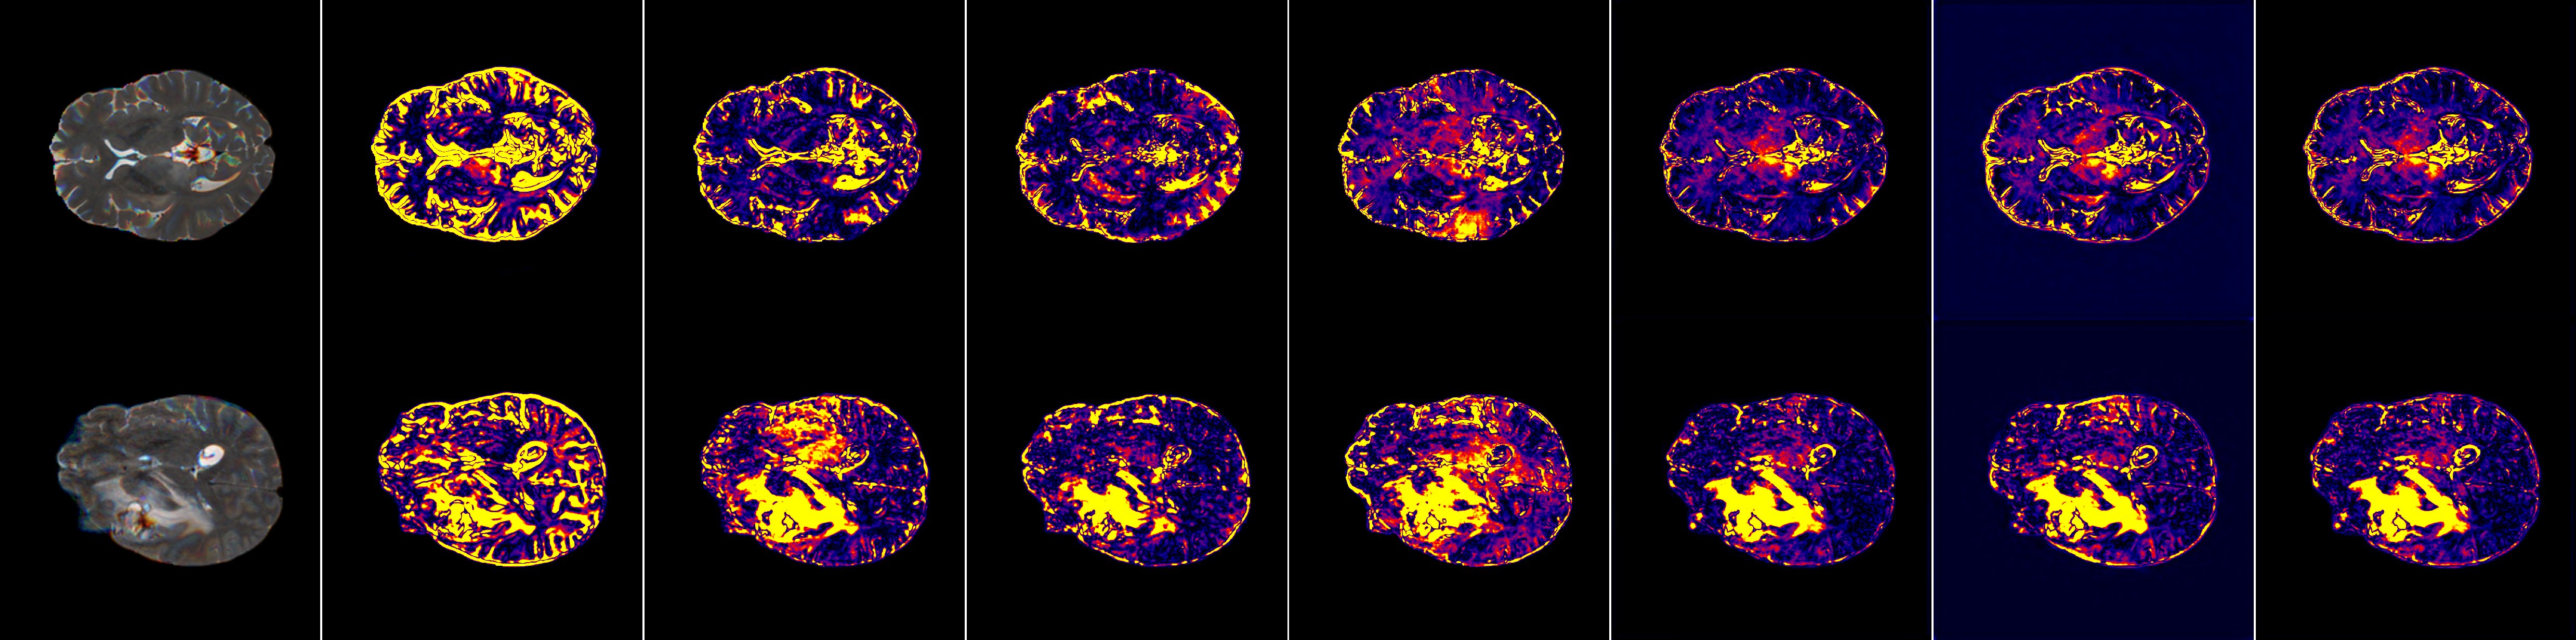

Refer to caption

Figure 5: Error heatmaps illustrating the discrepancies between the outputs of quantitative comparison methods and the target images. Darker regions represent smaller errors, while brighter regions represent larger errors.

To validate the effectiveness of SRU-Pix2Pix, we selected a range of representative models for comparison, including adversarial-based methods such as CycleGAN [19] and Pix2Pix [18], structurally enhanced architectures such as NICE-GAN [16] and ResViT [24], and diffusion-based methods such as BBDM [30]. These approaches cover different paradigms, including unpaired translation, paired translation, hybrid architectures, and diffusion-based generation, providing a rigorous benchmark for comprehensively evaluating the performance of our proposed method.

As shown in Fig. 5, we perform thermal error analysis on images generated by CycleGAN [19] and Pix2Pix [18] based on adversarial generation, NICE-GAN [16] and ResViT [24] based on structural improvements, BBDM [30] based on the diffusion mechanism, as well as our proposed method, with the main experimental analysis conducted on this figure. To further demonstrate the consistency of these observations across different test cases, Fig. 67 present supplementary thermal error visualizations on the test dataset, where each row corresponds to a representative case and each column to a different method.

This visualization highlights the pixel-wise discrepancies between the generated outputs and the ground truth, where darker regions correspond to smaller errors and brighter regions indicate larger errors. Unsupervised adversarial generation methods, such as CycleGAN [19] and NICE-GAN [16] , tend to produce unstable local reconstructions, often failing to capture fine details accurately. Supervised adversarial methods, such as Pix2Pix [18], benefit from paired training data and can recover most local details, yet they still struggle to generate precise edge structures. Hybrid structural models (e.g., ResViT [24]) further improve boundary reconstruction, but noticeable gaps remain compared to the ground truth.

Diffusion-based methods, such as BBDM [30], generate smoother intensity distributions and generally achieve high structural fidelity and intensity accuracy. However, due to global sampling across the entire image, these methods also tend to reconstruct irrelevant background regions, resulting in higher background errors. Consequently, BBDM [30] demonstrates strong performance in quantitative metrics including PSNR [35], LPIPS [36], MS-SSIM [37], MSE [38], and NMSE [38], while its SSIM [35] performance is relatively inferior.

Our method achieves a more balanced performance across detail fidelity, structural accuracy, and background robustness. The incorporation of SEResNet modules enables the network to more precisely capture local details and edge information, while the U-Net++ [31] architecture effectively mitigates the background reconstruction artifacts observed in diffusion models. As a result, our method achieves consistently lower error regions, demonstrating stronger generalization and robustness. Our proposed framework not only reduces background noise and structural distortions but also enhances the preservation of clinically relevant features. This advantage underscores the potential of our approach for reliable medical image modality translation, where both global consistency and fine-grained local accuracy are crucial. Detailed quantitative comparisons can be found in Table I to Table V.